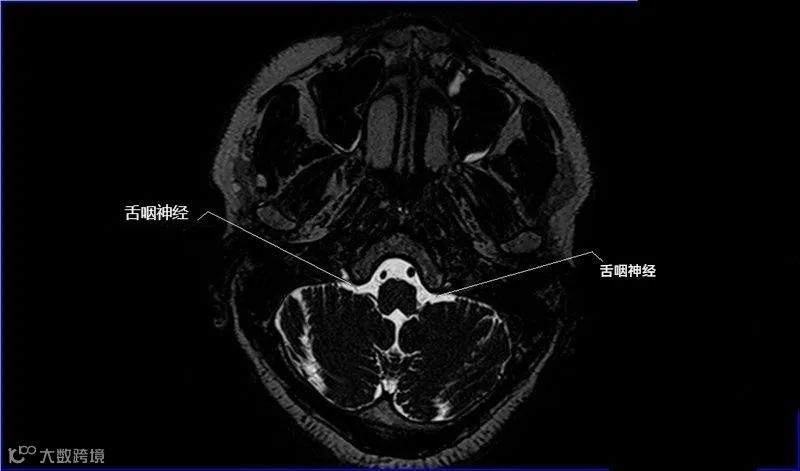

十二对脑神经口诀

一嗅二视三动眼,四滑五叉六外展,

七面八听九舌咽,迷走及副舌下全。